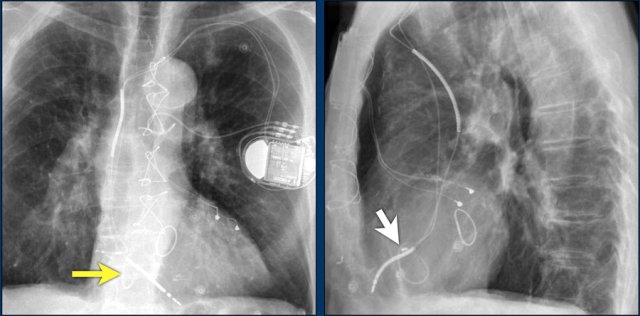

The findings are:

• Two epicardial leads connected to pacemaker

• ICD

• two leads to right ventricular apex

• one lead contains two shock coils

• tricuspid valve (arrows)

• mitral valve